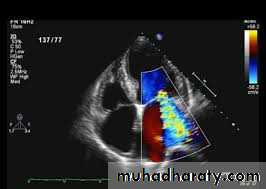

2D Echo cardiography –

valve edema ,mitral regurgitation, LA & LV dilatation, pericardial effusion, decreased contractility.